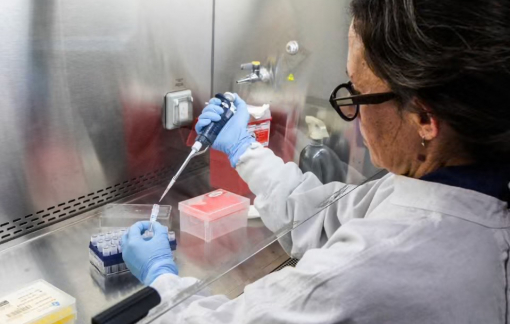

Một loại thuốc thử nghiệm mới mang đến hy vọng cho bệnh nhân ung thư sau khi cho thấy khả năng thu nhỏ khối u hiệu quả.

Một loại thuốc tiêm điều trị ung thư đang mang đến hy vọng mới cho những bệnh nhân đã không còn đáp ứng với các phương pháp điều trị thông thường.

Một xét nghiệm bộ gen mới được đánh giá là bước đột phá trong điều trị ung thư vú sẽ giúp hàng triệu phụ nữ trên thế giới tránh được hóa trị.

Các nhà khoa học vừa tìm ra phương pháp tiêu diệt các tế bào "xác sống" gây ung thư và lão hóa, mở ra hy vọng cho các liệu pháp mới.